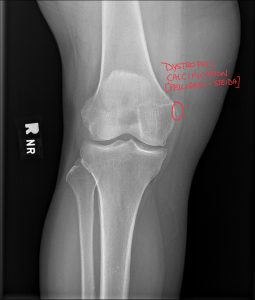

We are committed to enhancing patient care by delivering top-tier medical imaging evaluations and reports consistently. Our team of board-certified radiologists brings specialized expertise in diagnostic imaging, with a particular focus on chiropractic radiology that specializes in spine and musculoskeletal imaging. We strive to provide not just readings, but invaluable consultations, ensuring each patient receives the best that modern radiology has to offer. Our dedication to accuracy, speed, and reliability in off-site image interpretations sets us apart as trusted partners in healthcare.